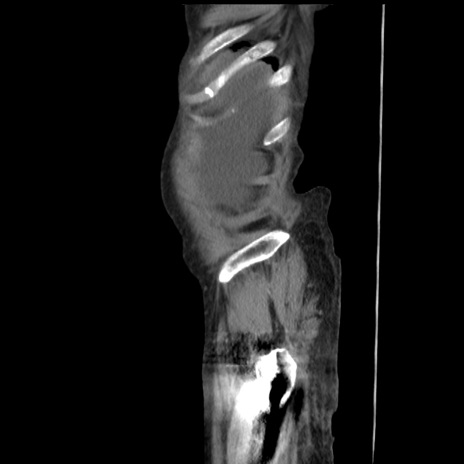

症例31(矢状断像)

【症例】80歳代 女性

【主訴】腹部膨満感

【現病歴】他院にて肝硬変にてフォロー中。1週間前から便秘、腹部膨満感、臍部腫瘤あり受診となる。

【既往歴】肝硬変

【身体所見】腹部膨隆あり、皮膚変化なし、疼痛なし。

【データ】WBC 4600、CRP 0.25